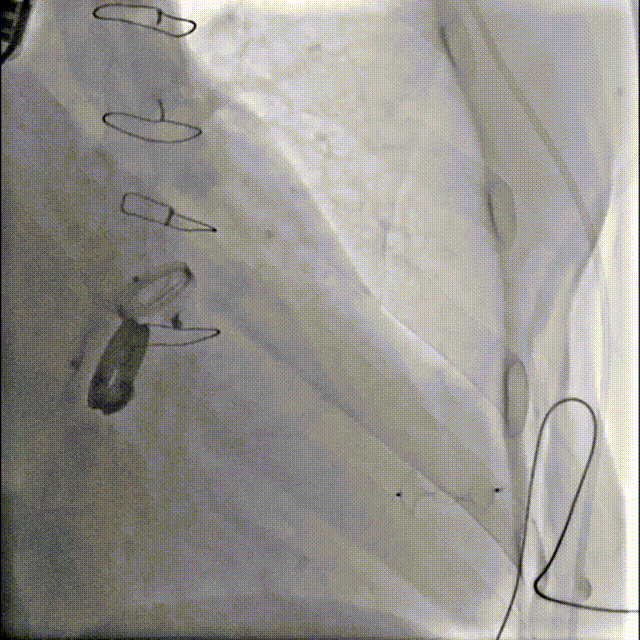

患者二尖瓣机械瓣瓣周可见两处间隙,分别位于10点位、1-2点位,大小分别约为:10点位7×5mm,1-2点位10×4mm,彩色血流提示二尖瓣位瓣周返流(两束,大量),主动脉瓣位机械瓣上血流速度正常,瓣周未见明显返流。

心脏超声可见两处二尖瓣瓣周漏

1.患者平卧位,食道超声检查瓣周漏位置及大小,并引导穿刺心尖,选择7F鞘管通过10点位置瓣周漏口,将单弯导管送入左心室,置换超硬导丝至左心室,选择12-14mmPDAO封堵10点位漏口。